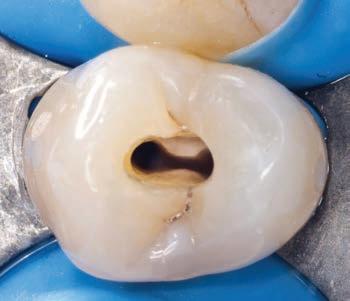

Figure 15, 16 &17: Views of the monolithic restoration in lithium disilicate, polished and finished.

Additionally, the ultra-thin structure of the Initial LiSi Block permits easily polishing of the restoration even after the occlusal adjustments, leaving the area extremely uniform and smooth. This reduces the finishing times, the brightness lasts longer and the occlusal contacts produce less abrasion of the restoration and of the antagonists (Figs. 15-17).

As a consequence of the newly surgically modified prosthetic margin, the appropriate length of the abutment for an adhesive cementation had been obtained, and the high aesthetic requirement and the contemporary need of containing costs with a monolithic crown, led the clinical choice to a lithium-disilicate crown with high translucency and suitable for the CAD-CAM technology.

The chosen material was the Initial LiSi Block™ (GC), because the ultra-thin structure of the Initial LiSi Block’s has two important advantages: first of all, the block is easy to be milled with the use of chairside milling machine in the lab, and secondly this material doesn’t require other steps in the

oven to be sintered or glazed. In fact, Initial LiSi Block is the first completely crystalized lithium-disilicate block, so the time for its crystallization could be saved and the software for the finishing and glazing would not have to compensate for any material contraction due to the temperature in the

In this way, margins remain extremely thin and clear and it’s particularly useful in this case. It’s also possible to reduce costs compared to the use of a highly aesthetic and functional material.